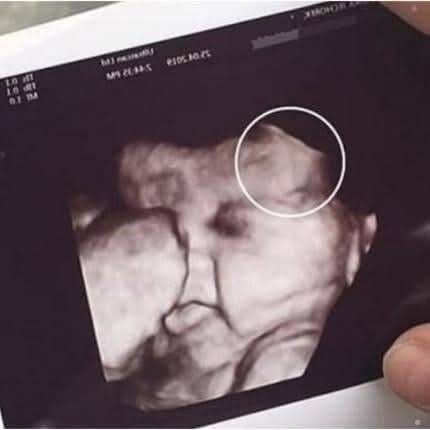

When 29-year-old Emily Foster, from Kent, England, arrived for her routine 20-week pregnancy scan, she expected the usual joy — a quick glimpse of her baby, a few happy tears, and perhaps a keepsake photo. But halfway through the scan, the technician suddenly laughed.

“Is that… hair?” she asked in disbelief.

On the black-and-white monitor, Emily’s unborn daughter already appeared to have a fuzzy halo around her head. Even the doctor joined in the laughter: “Looks like you’ve got a little rock star in there!” Neither of them could have guessed just how true that prediction would be.